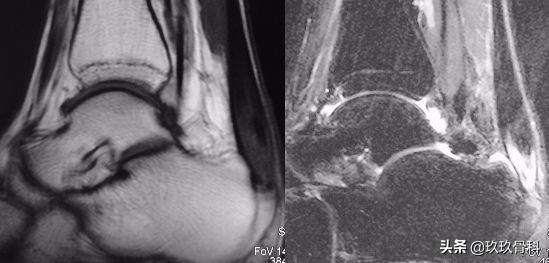

- MRI

应力位片